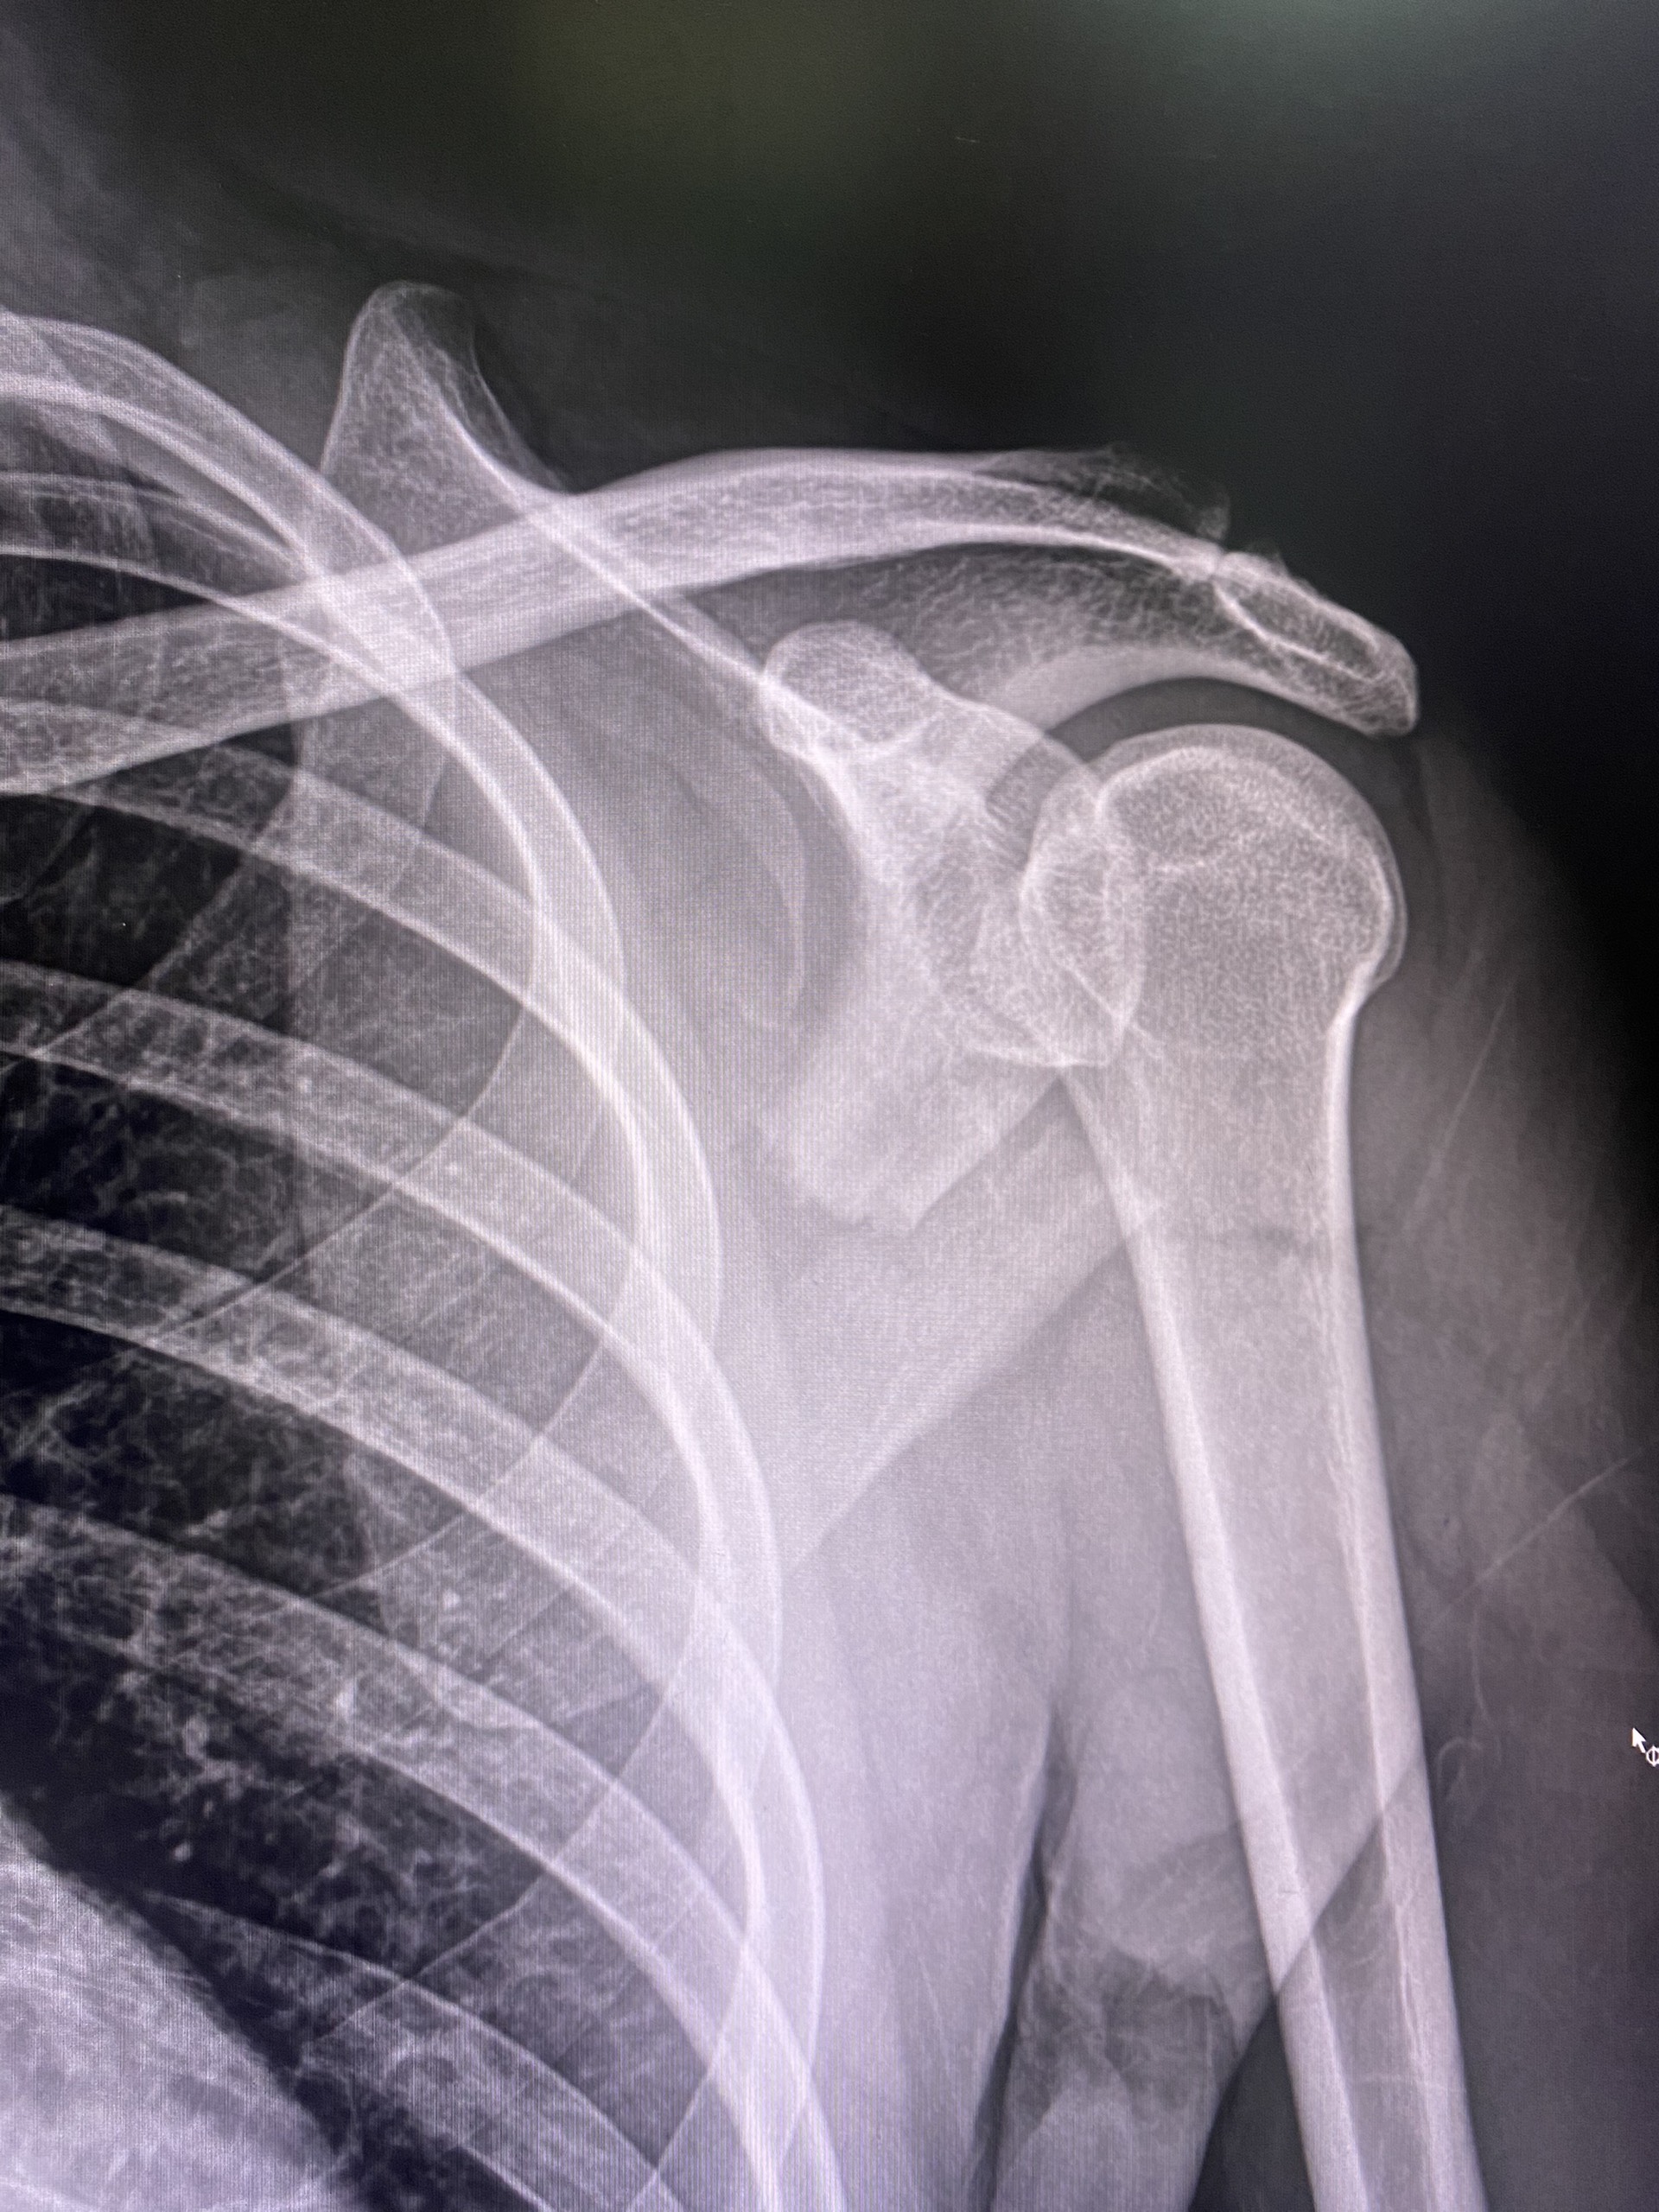

Chiều ngày 17/4/2023, anh D.K.C 39 tuổi ở khu Xuân Thắng, xã Mỹ Lung, huyện Yên Lập khi đang đi làm tại Hà Nội đã không may bị ngã xe máy. Sau ngã thấy sưng đau vai trái, không nhấc được tay trái lên, cử động khó. Người bệnh được gia đình đưa đến Trung tâm Y tế huyện Yên Lập vào 20h cùng ngày. Qua thăm khám lâm sàng và kết quả chụp CT-Scanner cho thấy hình ảnh gãy vỡ phức tạp xương bả vai trái. Được chẩn đoán: Gãy vỡ phức tạp xương bả vai trái, xử trí cố định khớp vai trái bằng áo nửa thân và điều trị nội khoa đến khi hết nề.

Sau một tuần điều trị, người bệnh tỉnh táo, huyết động ổn định, vùng vai nề nhẹ, đỡ đau nhức. Được chỉ định phẫu thuật kết hợp xương vai bằng nẹp vít. Người bệnh và người nhà đồng ý thực hiện phẫu thuật.